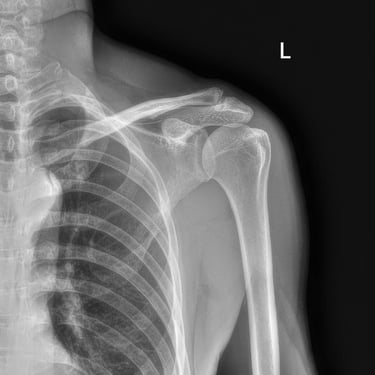

Radiología humana

Brindamos servicios de radiología humana a domicilio, orientados a facilitar el acceso a estudios radiográficos de calidad sin traslados innecesarios. Esta modalidad es ideal para pacientes con movilidad reducida, adultos mayores, instituciones de salud y zonas rurales. El servicio se realiza con equipos de radiología móvil, priorizando la calidad de imagen, la precisión diagnóstica y la seguridad radiológica. Cada estudio se desarrolla con atención personalizada y por profesionales con experiencia en el cuidado de la salud y seguridad del paciente.